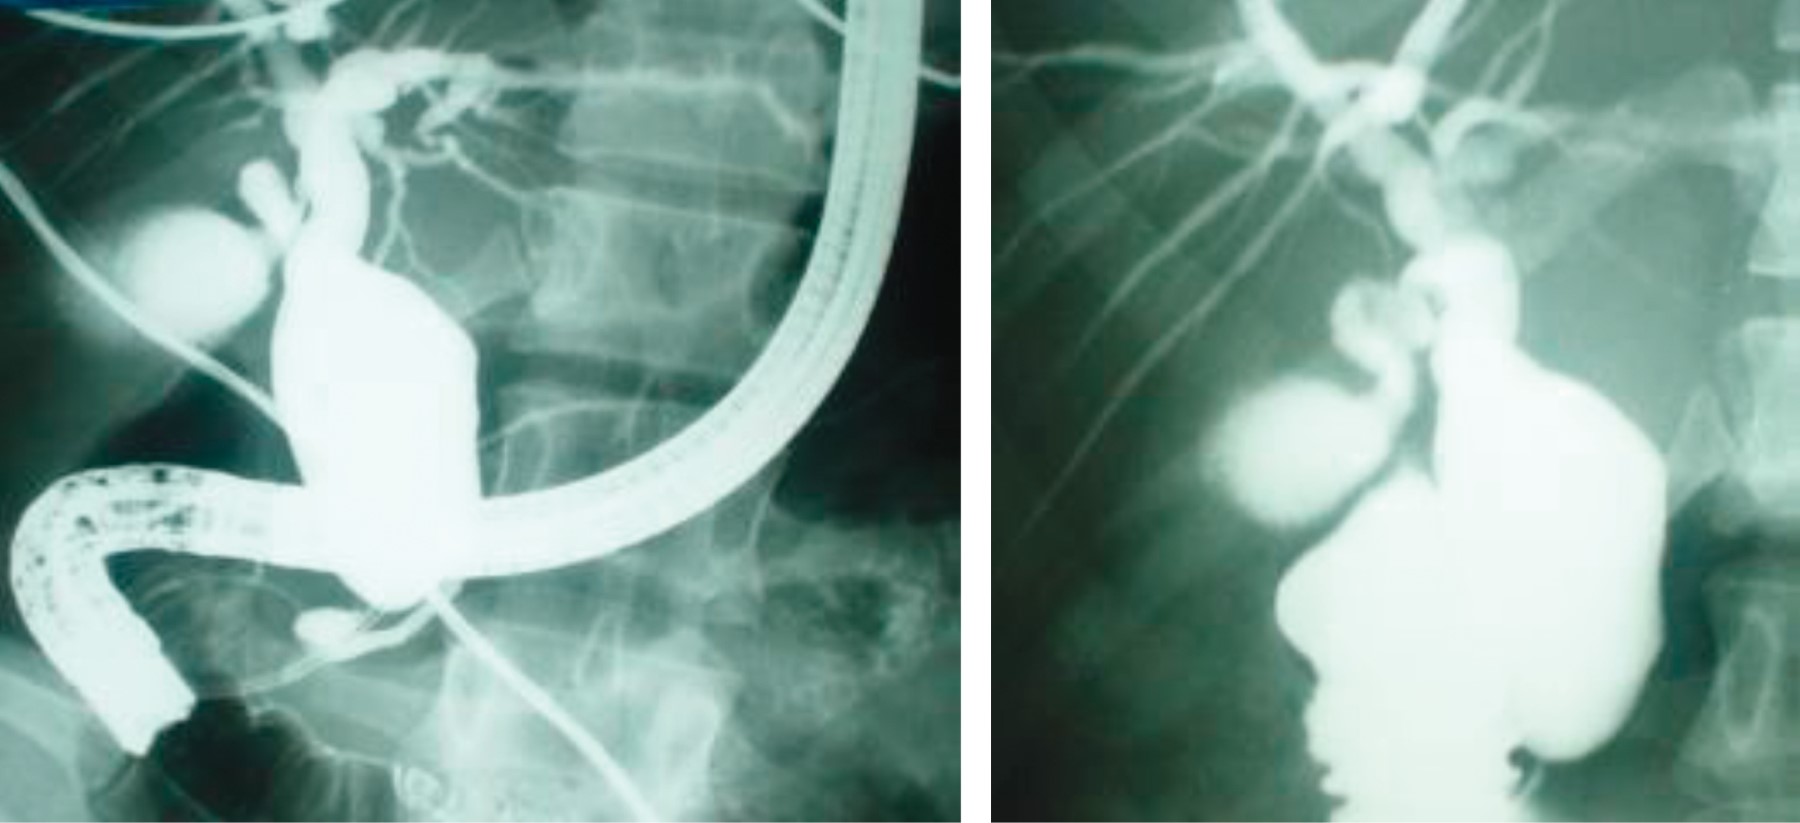

After her informed consent was obtained and preoperative surgical protocol was completed, an endoscopic retrograde cholangiopancreatography was programmed, as it is the resource available in our institution, with the following report.

Endoscopic retrograde cholangiopancreatography: a fusiform cystic dilatation of the distal common bile duct of 2.8 cm in its widest portion that begins 1.6 cm below the confluence of the hepatic ducts at the level of the cystic junction was seen, extending for 4.8 cm, and ending in a segment of a narrow common bile duct that is insufficient to empty the cyst. The gallbladder was partially opacified, and the common hepatic duct, the carina, and both right and left hepatic ducts had normal diameter and configuration; the intrahepatic biliary tract was normal (Figure 4).

Diagnostic impression: the preoperative diagnosis was that of a fusiform solitary common bile duct cyst type I (Todani's classification). Once the preoperative protocol was completed and the anatomy of the cyst was defined, as well as its classification and relationship with adjacent structures, elective surgery was performed.